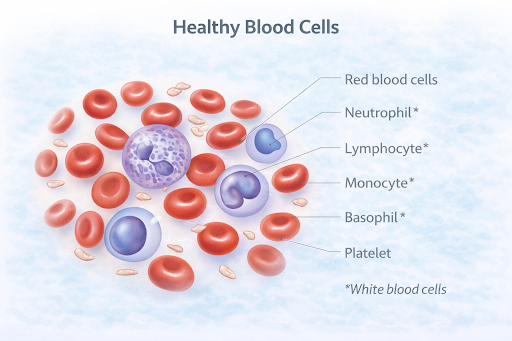

What are Blood Cancers and Lymphomas?

Blood cancers are a group of cancers that affect the blood, bone marrow, or lymphatic system. Lymphomas are a type of blood cancer that primarily involves the lymphatic system, which plays an important role in immunity. These cancers occur when certain blood-forming or immune cells begin to grow and behave abnormally.

Blood cancers are a group of cancers that affect the blood, bone marrow, or lymphatic system. Lymphomas are a type of blood cancer that primarily involves the lymphatic system, which plays an important role in immunity. These cancers occur when certain blood-forming or immune cells begin to grow and behave abnormally.

How does it develop?

These cancers typically develop when blood or immune cells undergo genetic changes that alter their growth and division. Instead of maturing normally, these cells may multiply uncontrollably and fail to function properly. Over time, they can crowd out healthy cells or interfere with normal immune responses.

Leukaemia: Types and Staging

Types of Leukaemia

Leukaemia is commonly grouped based on how quickly it develops and the type of blood cell involved.

Leukaemia is also classified by the blood cell affected:

Leukaemia: Types and Staging

Types of Leukaemia

Leukaemia is commonly grouped based on how quickly it develops and the type of blood cell involved.

Leukaemia is also classified by the blood cell affected:

- Lymphocytic Leukaemia – affects lymphocytes

- Myeloid Leukaemia – affects myeloid cells